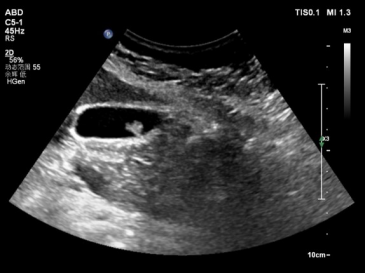

腹部超声可以准确地显示病变的大小、位置、数量和胆囊情况。目前,临床对胆囊息肉样病变的诊断主要是通过超声来检查。在超声检查中可显示:胆囊壁息肉样病变不随体位改变而移动,息肉样病变后方无声影,可单发或多发,较大的胆囊息肉样病变可显示有无明显血流信号。超声检查并不能揭示息肉的病理性质,对于较大的胆囊息肉样病变或怀疑恶变者,可通过超声造影、增强CT或MRI等检查与胆囊腺瘤、胆囊癌相鉴别。